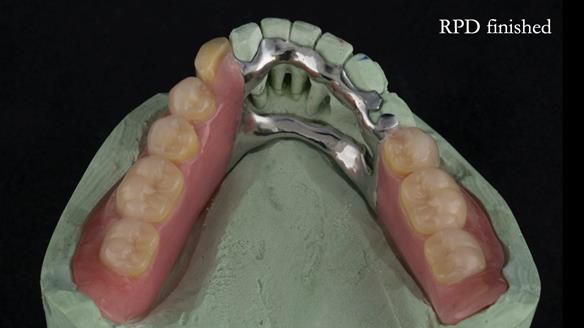

A metal-based upper RPD was made,

with metal backings incorporated to future-proof the design

should further teeth fail.

This case was always about function, not aesthetics.

Ken’s teeth were never going to look perfect.

There were stained composites, old restorations, and obvious wear.

That was accepted from the outset.

What matters is that the dentures worked.

The way Rowan lengthened the teeth — particularly in the upper RPD — to match the existing gingival recession on the remaining teeth was superb. The dentures sit naturally within the context of the rest of the mouth.

Most importantly, Ken could eat comfortably, speak normally, and get on with his life without thinking about his teeth. There were no ongoing problems. No drama. No repeated interventions.